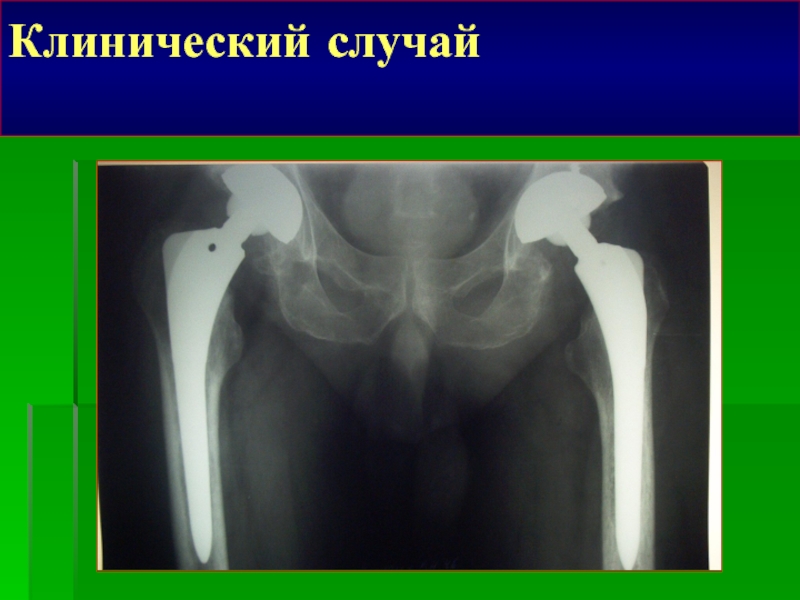

Клинический случай

Больная 38 лет, Двухсторонний ДКА.

Клинический случайБольная 38 лет, Двухсторонний ДКА.